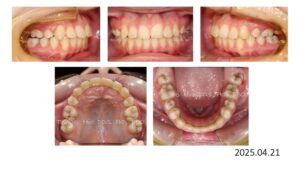

治療が終わりました。

動的治療期間は 1年 9か月です。